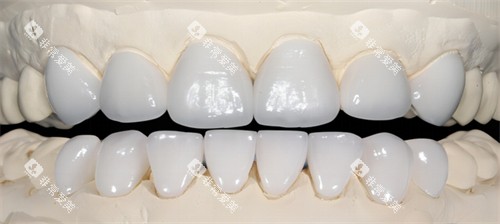

全瓷冠:2000-3500元/颗

烤瓷冠:800-1500元/颗

金属冠:500-800元/颗

嵌体修复:1500-3000元/颗